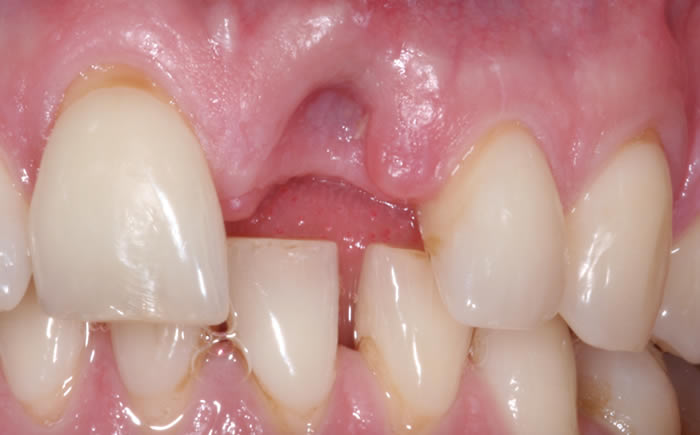

Before & After Gallery

More front teeth replaced by dental implants

Case Three (4 images)